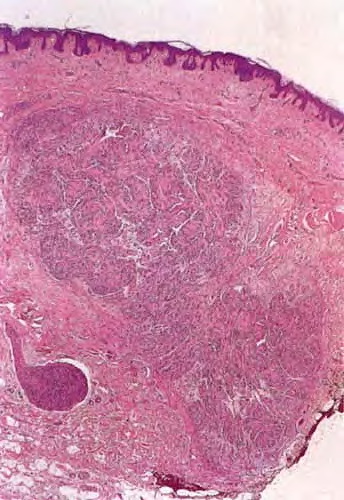

Schwannoma (neurilemmoma) = الشوانوم = ورم غمد الليف العصبي